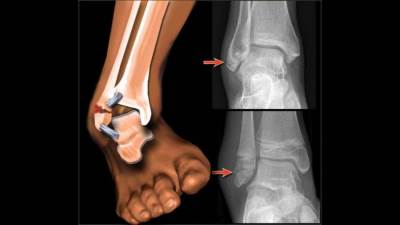

وصمم الكاحل الصناعي، الذي يزود بمحرك وبطاريات ويعمل بكفاءة تزيد 20 في المائة عن كفاءة أي كاحل صناعي معروف، هيو هير الذي ظل يحاول انتاج نوع مطور منه بعد ان تعرض كاحلاه للكسر اثناء تسلقه الصخور الوعرة قبل ربع قرن.

وتعرف الكواحل الصناعية السابقة بأنها خاملة لأنها لا تستطيع دفع ارجل مستخدميها، ولذلك فانها تجهدهم اثناء الحركة، وتؤدي الى فقدان نحو 30 في المائة من طاقتهم اثناء المشي بها. اما الكاحل الجديد فقد صمم على مبدأ عمل الكاحل الطبيعي، حيث وأثناء مشي الانسان تقوم الاوتار والروابط في الرجل باختزان الطاقة المتولدة عن ضرب القدم للارض كي تستخدمها لدفع الرجل الى الامام.

ونجح مصممو الكاحل الجديد في وضع عدد النوابض التي تعمل سوية مع محرك صغير. ويختزن احدها الطاقة الحركية اثناء حركة الشخص الماشي، كي تتحرر لاحقا عند انتهاء عملية ضرب القدم للارض. وقال هير ان «الفرق بين الكاحل الجديد والتقليدي يمكن ان تشبه بعملية الوقوف على مشى اوتوماتيكي متحرك في المطار» وهو يتوقع ان ينتج الكاحل على نطاق تجاري العام المقبل.